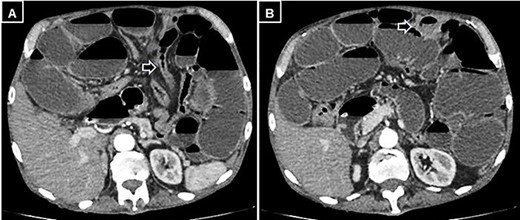

A supine and upright plain X-ray of the abdomen were obtained and showed dilated small bowel loops, mainly in the left upper abdomen, along with multiple air-fluid levels (Fig. 1). Computed tomography (CT) demonstrated significant air-fluid distention of the entire small bowel, up to the right flank and periumbilical region, where a change in caliber was observed (Fig. 2). The findings corresponded to small bowel obstruction (Fig. 3).

Abdominal and pelvic CT with intravenous contrast. (A) Axial image illustrating a change in caliber (black arrow) with subsequent distension of the small intestine, and (B) a small mesenteric collection (black arrow).